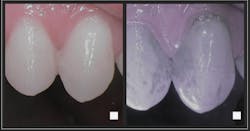

- Trujillo K, Räisänen IT, Sorsa T, Pätilä T. Repeated daily use of dual-light antibacterial photodynamic therapy in periodontal disease—a case report. Dent J (Basel). 2022;10(9):163. doi:10.3390/dj10090163